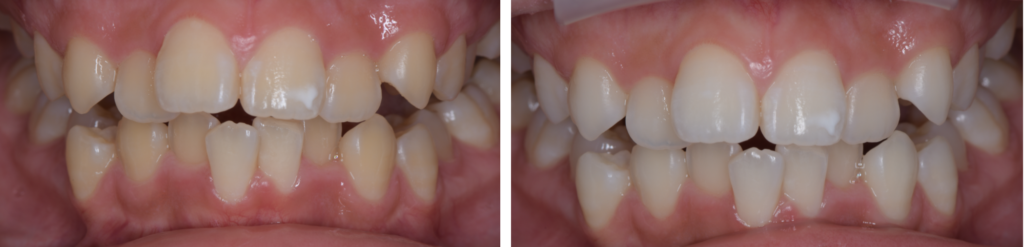

• オールセラミックス審美治療

CASE

墨田区・菊川駅の歯医者「菊川駅前歯科」は、患者様と共に妥協のない

『最善の治療』を叶えていく歯科医院です。

患者の個々の状態に合わせて材料・薬剤を選択し、研鑽を積んだ高い技術力で、歯を抜かずに守り美しく健康なお口の維持を実現すべく、患者様それぞれのお口の状態やお悩みに合わせた最適な治療方法をご提案いたします。

全顎治療(フルマウス治療)では、歯の健康だけではなく、見た目の美しさも重視しております。